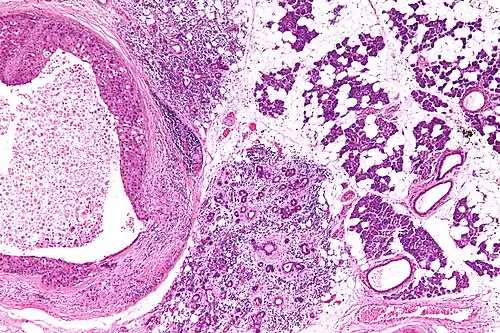

Clinicamente, apresenta-se como uma massa de crescimento lento e assintomático por muitos anos, e é raramente associado a cilindromas dermais.[2] Não possui características radiográficas marcantes, e histologicamente é semelhante ao adenoma de células basais, mas com evidências de um padrão de crescimento invasivo, apresentando um parênquima tumoral de células ductais ao centro e organização em paliçada, com possível diferenciação escamosa ou sebácea e áreas de necrose.[2]